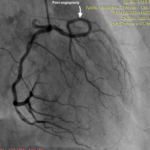

India’s First Transradial Rotablation with Rotapro Device for LMS PCI (25 April 2022)

India’s first successful LMS rotablation using the Rotapro device through the transradial route.